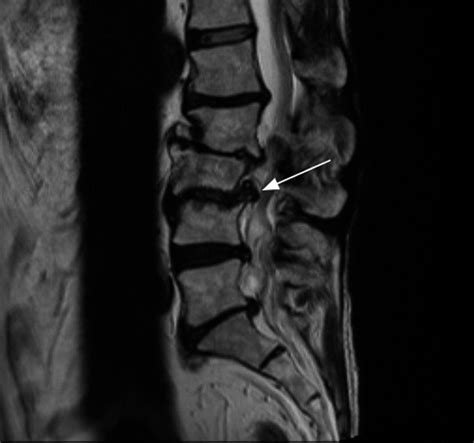

- Resonancia Magnética (RM): Es la técnica de imagen principal para visualizar con detalle los tejidos blandos de la columna, incluyendo los discos intervertebrales. Permite una evaluación detallada de la hernia.

- Tercera etapa: Se produce la extrusión del disco, donde la cápsula fibrosa se agrieta o se delamina, permitiendo que el núcleo pulposo se desplace significativamente.